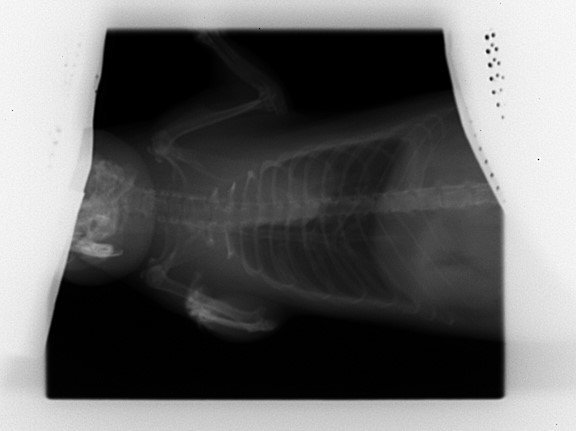

Découverte de multiples foyers infectieux dans les poumons :

Par radio, en janvier 2022.

A ce stade le véto n'est pas inquiet, car bien que multiples les tâches sont très infimes et les poumons restent intègres ; il me recommande de la surveiller de très près et me prévient que si une décompensation doit se faire se sera surement silencieusement (donc surveillance du poids et du mouvement respiratoire).

Le 25 mai je fais faire les radios de contrôle car je la trouve un chouya plus fine des flancs et on observe que l'aspect des foyers infectieux est plus "moucheté" ; c'est pas la cata encore (poumons toujours intègres) mais comme y'a tout de même évolution on commence le traitement : Doxy pour au moins deux semaines.

Voilà les radios ; pour chaque ligne :

• à gauche = janvier

• à droite = mai

KISS 2022 01 03 (1).jpgKISS 2022 05 25 (2).jpg

KISS 2022 01 03 (2).jpgKISS 2022 05 25 (1).jpg

• La radio montre que son cœur est légèrement décollé de l'endroit où il devrait être, mais sans que ça soit un soucis.